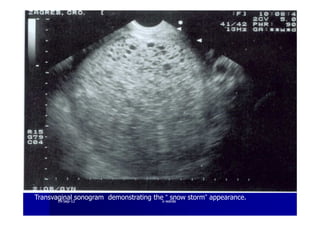

Ultrasound is the criterion standard forUltrasound is the criterion standard for

molar pregnancies. The classic imagemolar pregnancies. The classic image

is of ais of a ““snowstormsnowstorm”” patternpattern

A sonographic findings of a molar pregnancy. The

characteristic “snowstorm” pattern is evident.

Transvaginal sonogram demonstrating the “ snow storm” appearance.1919--SepSep--1212 o wardao warda